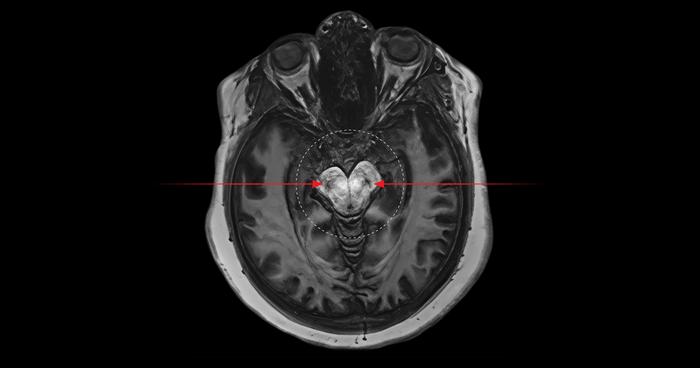

Researchers found those with cannabis use disorder exhibited an increase of neuromelanin (blacker spots) in a particular region of the midbrain associated with psychosis –the substantia nigra and ventral tegmental areas.

Using a non-invasive brain imaging technique called neuromelanin-sensitive magnetic resonance imaging, researchers were able to look at a substance called neuromelanin – a black pigment left behind in the brain that accumulates over time if there is too much dopamine. The neuromelanin appears in the scans as black spots, acting as a marker to measure and identify areas with dopamine activity.

“In people partaking in excess cannabis use, those spots are blacker than what they should be for their age compared to healthy individuals. This indicates they have high levels of dopamine, and in some cases are showing pigments someone 10 years older would have,” said Palaniyappan, who is also a professor at McGill University.

"We saw an increase of blacker spots in a particular region of the midbrain associated with psychosis –the substantia nigra and ventral tegmental areas. This increase was seen in those with cannabis use disorder regardless of whether they have first-episode schizophrenia,” said Ali Khan, Schulich Medicine & Dentistry professor and scientist at Robarts Research Institute.